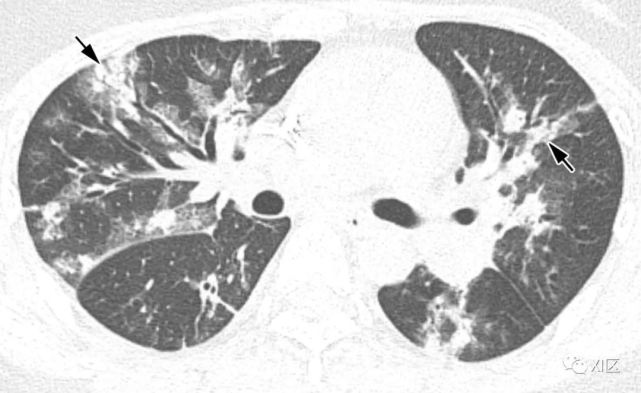

图片

图15 27岁男性,HIV患者,高热三天。没有麻疹和免疫史。诊断为麻疹病毒肺炎。入院第11天的胸部CT图像显示双侧异常,包括小叶间隔增厚(肺尖部;B,箭)、支气管壁厚、多发大小不等的结节(分叉部;C,箭)、胸膜增厚(基底部;D,箭),以及弥漫性毛玻璃影,而第8天的胸片显示左肺出现毛玻璃影(A)。麻疹相关性肺炎的明确诊断基于三项发现:(1)体检发现;(2)微生物测试结果;和(3)典型的CT表现。